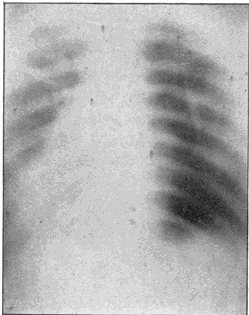

Fig. 1.—Head.

Fig. 2.—Broken Arm, Overlapping.

(Due to defective setting.)

Fig. 3.—Ribs.

Fig. 4.—Knee, Knickerbocker Buttons, Bullet in Femur.

| 206. | Elements of the Thorax. | Morton |

| 207. | A Colles’ Fracture Detected by X-rays. | Morton |

| 208. | Motions of Liver, Outlines of Spleen, and Tuberculosis Indicated. | Morton and Williams |